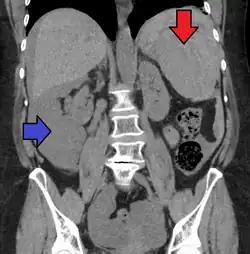

Traumatic rupture of the spleen on contrast enhanced axial CT (portal venous phase)

Splenic hematoma resulting in free abdominal blood

Splenic rupture is usually evaluated by FAST ultrasound of the abdomen.[5] Generally this is not specific to splenic injury; however, it is useful to determine the presence of free floating blood in the peritoneum.[5] A diagnostic peritoneal lavage, while not ideal, may be used to evaluate the presence of internal bleeding a person who is hemodynamically unstable.[6] The FAST exam typically serves to evaluate the need to perform a CT scan.[6] Computed tomography with IV contrast is the preferred imaging study as it can provide high quality images of the full peritoneal cavity.[5]